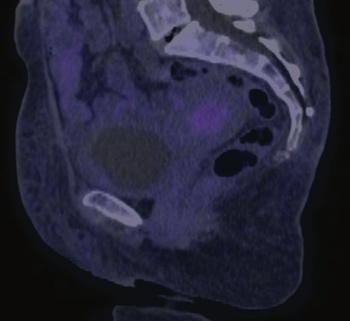

In this edition of Clinical Quandaries Eder A. Arango Bravo, MD, and colleagues present a 63 year old woman who has cervical cancer with kidney failure and additional comorbidities.